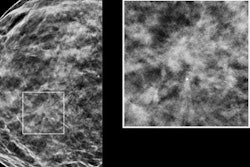

Radiologists have found that generating synthetic 2D digital mammography images with digital breast tomosynthesis (DBT) is equivalent to using full-field digital mammography (FFDM) images for most women without suspicious findings on their mammograms, according to research presented at the Society of Breast Imaging (SBI) conference in Austin, TX.

The study included 649 patients who underwent screening between June and September 2015 on a full-field digital mammography device and a Hologic Selenia Dimensions digital breast tomosynthesis unit equipped with the company's C-View synthetic 2D software. Breast imagers compared the synthetic 2D images with the FFDM images using a five-point scale.